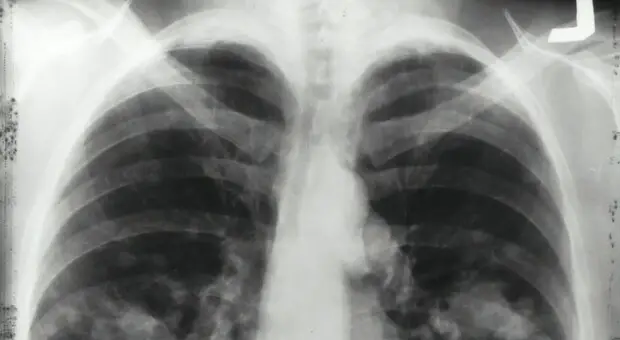

Tumore al polmone, al via alla prima terapia a bersaglio molecolare: la forma rara colpisce anche giovani e non fumatori

Una nuova cura per il cancro al polmone: via libera in Italia alla prima terapia a bersaglio molecolare per il trattamento adiuvante del carcinoma polmonare non a piccole cellule Alk-positivo ad alto...